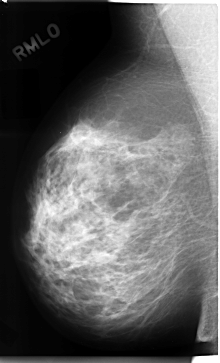

C_0080_1.RIGHT_MLO

RIGHT_CC LINES 4760 PIXELS_PER_LINE 2800 BITS_PER_PIXEL 12 RESOLUTION 50 NON_OVERLAY

RIGHT_MLO LINES 4712 PIXELS_PER_LINE 2848 BITS_PER_PIXEL 12 RESOLUTION 50 NON_OVERLAY